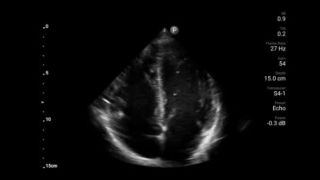

Get the clarity of larger ultrasound systems with Lumify

SonoCT reinforces real tissue imaging while eliminating random artifacts. This technology produces images superior to conventional imaging in up to 94% of patients.